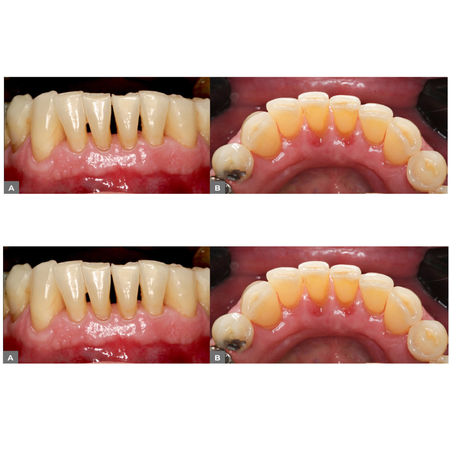

INTRODUÇÃO: O sulco radicular é uma anomalia de desenvolvimento caracterizada por uma invaginação linear que se estende da coroa em direção à raiz, podendo estar localizada na face vestibular ou palatina. Sua presença pode predispor a alterações periodontais e endodônticas, dificultando o diagnóstico e comprometendo o prognóstico. OBJETIVO: Este relato descreve o tratamento endodôntico- -periodontal de um incisivo lateral superior direito com dois sulcos radiculares profundos,...

INTRODUCTION: The radicular groove is a developmental anomaly characterized by a linear invagination extending from the crown toward the root, which may be located on either the buccal or palatal surface. Its presence may predispose to periodontal and endodontic complications, hindering diagnosis and compromising prognosis. OBJECTIVE: This report describes the endodontic-periodontal management of a maxillary right lateral incisor with two deep radicular grooves, one on the buccal and the...